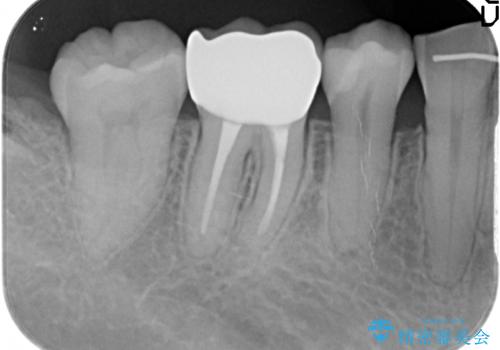

セラミッククラウン・セラミックインレーを用いた精密治療を計画します。

- 20.9万円(ジルコニアクラウン・仮歯 ・セラミックインレー)費用は治療当時の料金となります

審美性、化学的安定性に優れるセラミック治療を行うことができました。